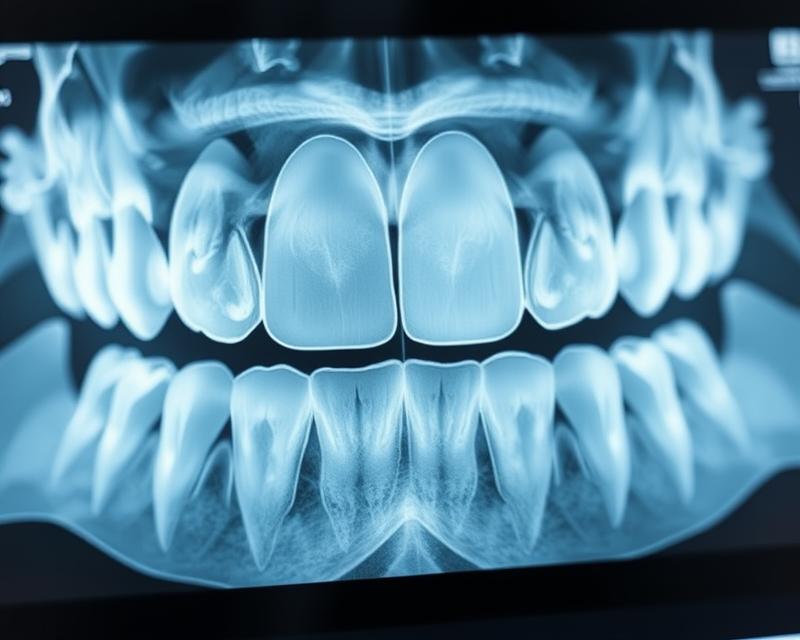

Rentgen stomatologiczny to kluczowe badanie diagnostyczne, które wykorzystuje promieniowanie X do szczegółowej oceny zębów oraz tkanek w jamie ustnej. Ta nieinwazyjna procedura dostarcza obrazów, obejmujących zęby, kości szczęki, a także tkanki okołowierzchołkowe. Dzięki niej lekarze mają nieocenione narzędzie w rozpoznawaniu próchnicy i stanów zapalnych, co pomaga w dokładnym identyfikowaniu potencjalnych problemów zdrowotnych.

RTG pantomograficzne, zwane także zdjęciem ortopantomograficznym, wykonuje panoramiczny obraz całej jamy ustnej, co umożliwia jednoczesne zobaczenie wszystkich zębów. Ten typ badania jest niezwykle przydatny zarówno w diagnostyce, jak i w planowaniu leczenia, a także potrafi ujawniać problemy, które mogłyby umknąć podczas analizy RTG punktowego.

RTG zębów to nieinwazyjna metoda diagnostyczna, która wykorzystuje promieniowanie rentgenowskie do dokładnego przeglądania tkanek. W trakcie badania promieniowanie przechodzi przez zęby oraz ich otoczenie, co pozwala uzyskać wyraźne i szczegółowe obrazy wnętrza jamy ustnej. Dzięki tej technologii dentyści mają możliwość oceny wielu ważnych aspektów zdrowotnych zębów i kości, co jest kluczowe w diagnozowaniu różnych schorzeń, w tym próchnicy.

Warto również zaznaczyć, że RTG zębów jest szybkim i bezbolesnym procesem. Technik umieszcza aparat w jamie ustnej pacjenta, a promieniowanie rejestruje obrazy na detektorze. Po zakończeniu badania wykwalifikowany personel dokładnie analizuje uzyskane obrazy, aby zdiagnozować ewentualne patologie lub inne zdrowotne problemy związane z uzębieniem. Pamiętaj, że odpowiednie przygotowanie pacjenta przed badaniem ma istotny wpływ na jakość otrzymywanych obrazów.